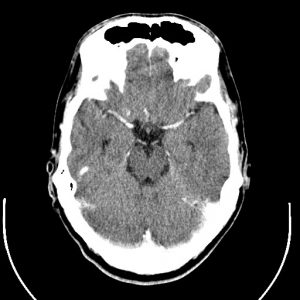

Para cada técnica de imágenes médicas, hay algoritmos especializados, ya que las características de las imágenes son diferentes, y su interpretación también. Por ejemplo, las imágenes de tomografía axial computarizada (TAC) pueden parecerse a las imágenes de resonancia magnética, sin embargo, la información que contienen es muy diferente, como se muestra a continuación.

Imágenes de TAC: se generan empleando rayos x y las formas e intensidades que se observan están relacionadas con la morfología y propiedades físicas de las estructuras anatómicas.

Imágenes de Resonancia: se crean a partir de campos magnéticos y contienen información relacionada con la actividad metabólica y el funcionamiento de los órganos y tejidos.

Izquierda: imagen de resonancia magnética del cerebro. Derecha, TAC del cerebro